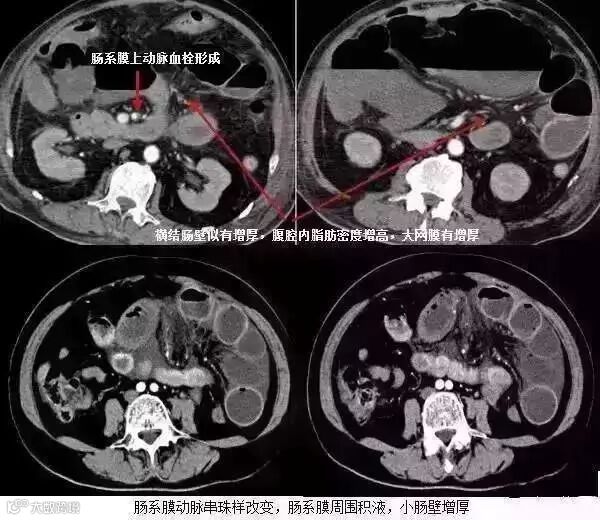

5肠系膜混浊征

肠系膜脂肪受炎症细胞、液体(水肿、淋巴液和血液)、肿瘤浸润及纤维化的CT表现。当肠系膜被液体或细胞浸润时,其脂肪CT值增加到-40~ -60HU(肠系膜脂肪的CT值类似于皮下及腹膜后脂肪,约-100~-160hu,肠系膜血管常呈横行或断面显示。),动、静脉失去锐利边缘。根据浸润的性质和范围,肠系膜血管可部分或完全模糊,顺着脏层腹膜常能发现肠系膜疾病的线索,在周围脂肪衬托下,肠系膜病变显示更加清晰。

上两幅图:肠系膜上动脉栓塞

下两幅图:十二指肠扭转致肠壁增厚、肠系膜水肿